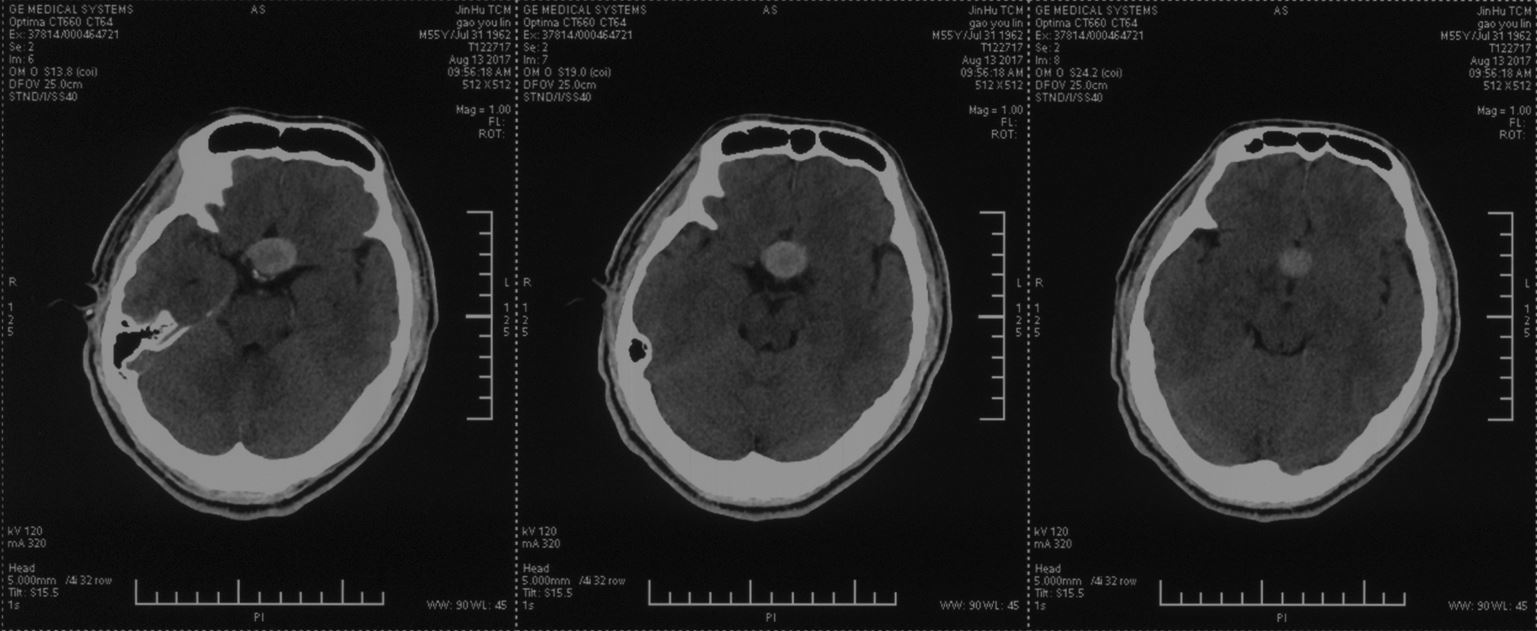

头颅CT示:鞍区占位性病变,局部高密度影,考虑垂体瘤卒中。

术后头颅CT示:鞍区干净无出血。